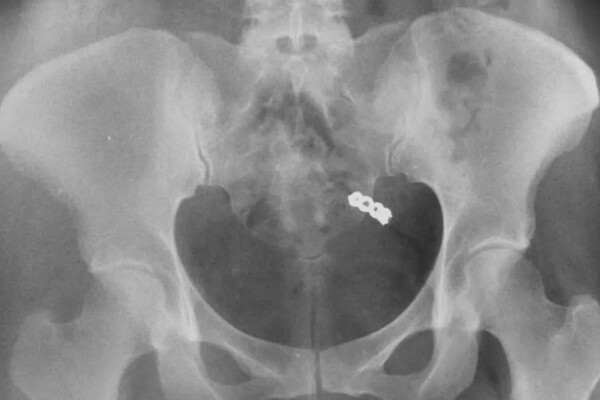

После тщательных поисков в гостиничном номере, Данна решила сделать рентген. Снимок показал, что кольцо действительно было внутри женщины. Врачи заверили ее, что переживать не нужно — украшение выйдет их организма естественным образом, что и произошло на следующий день.